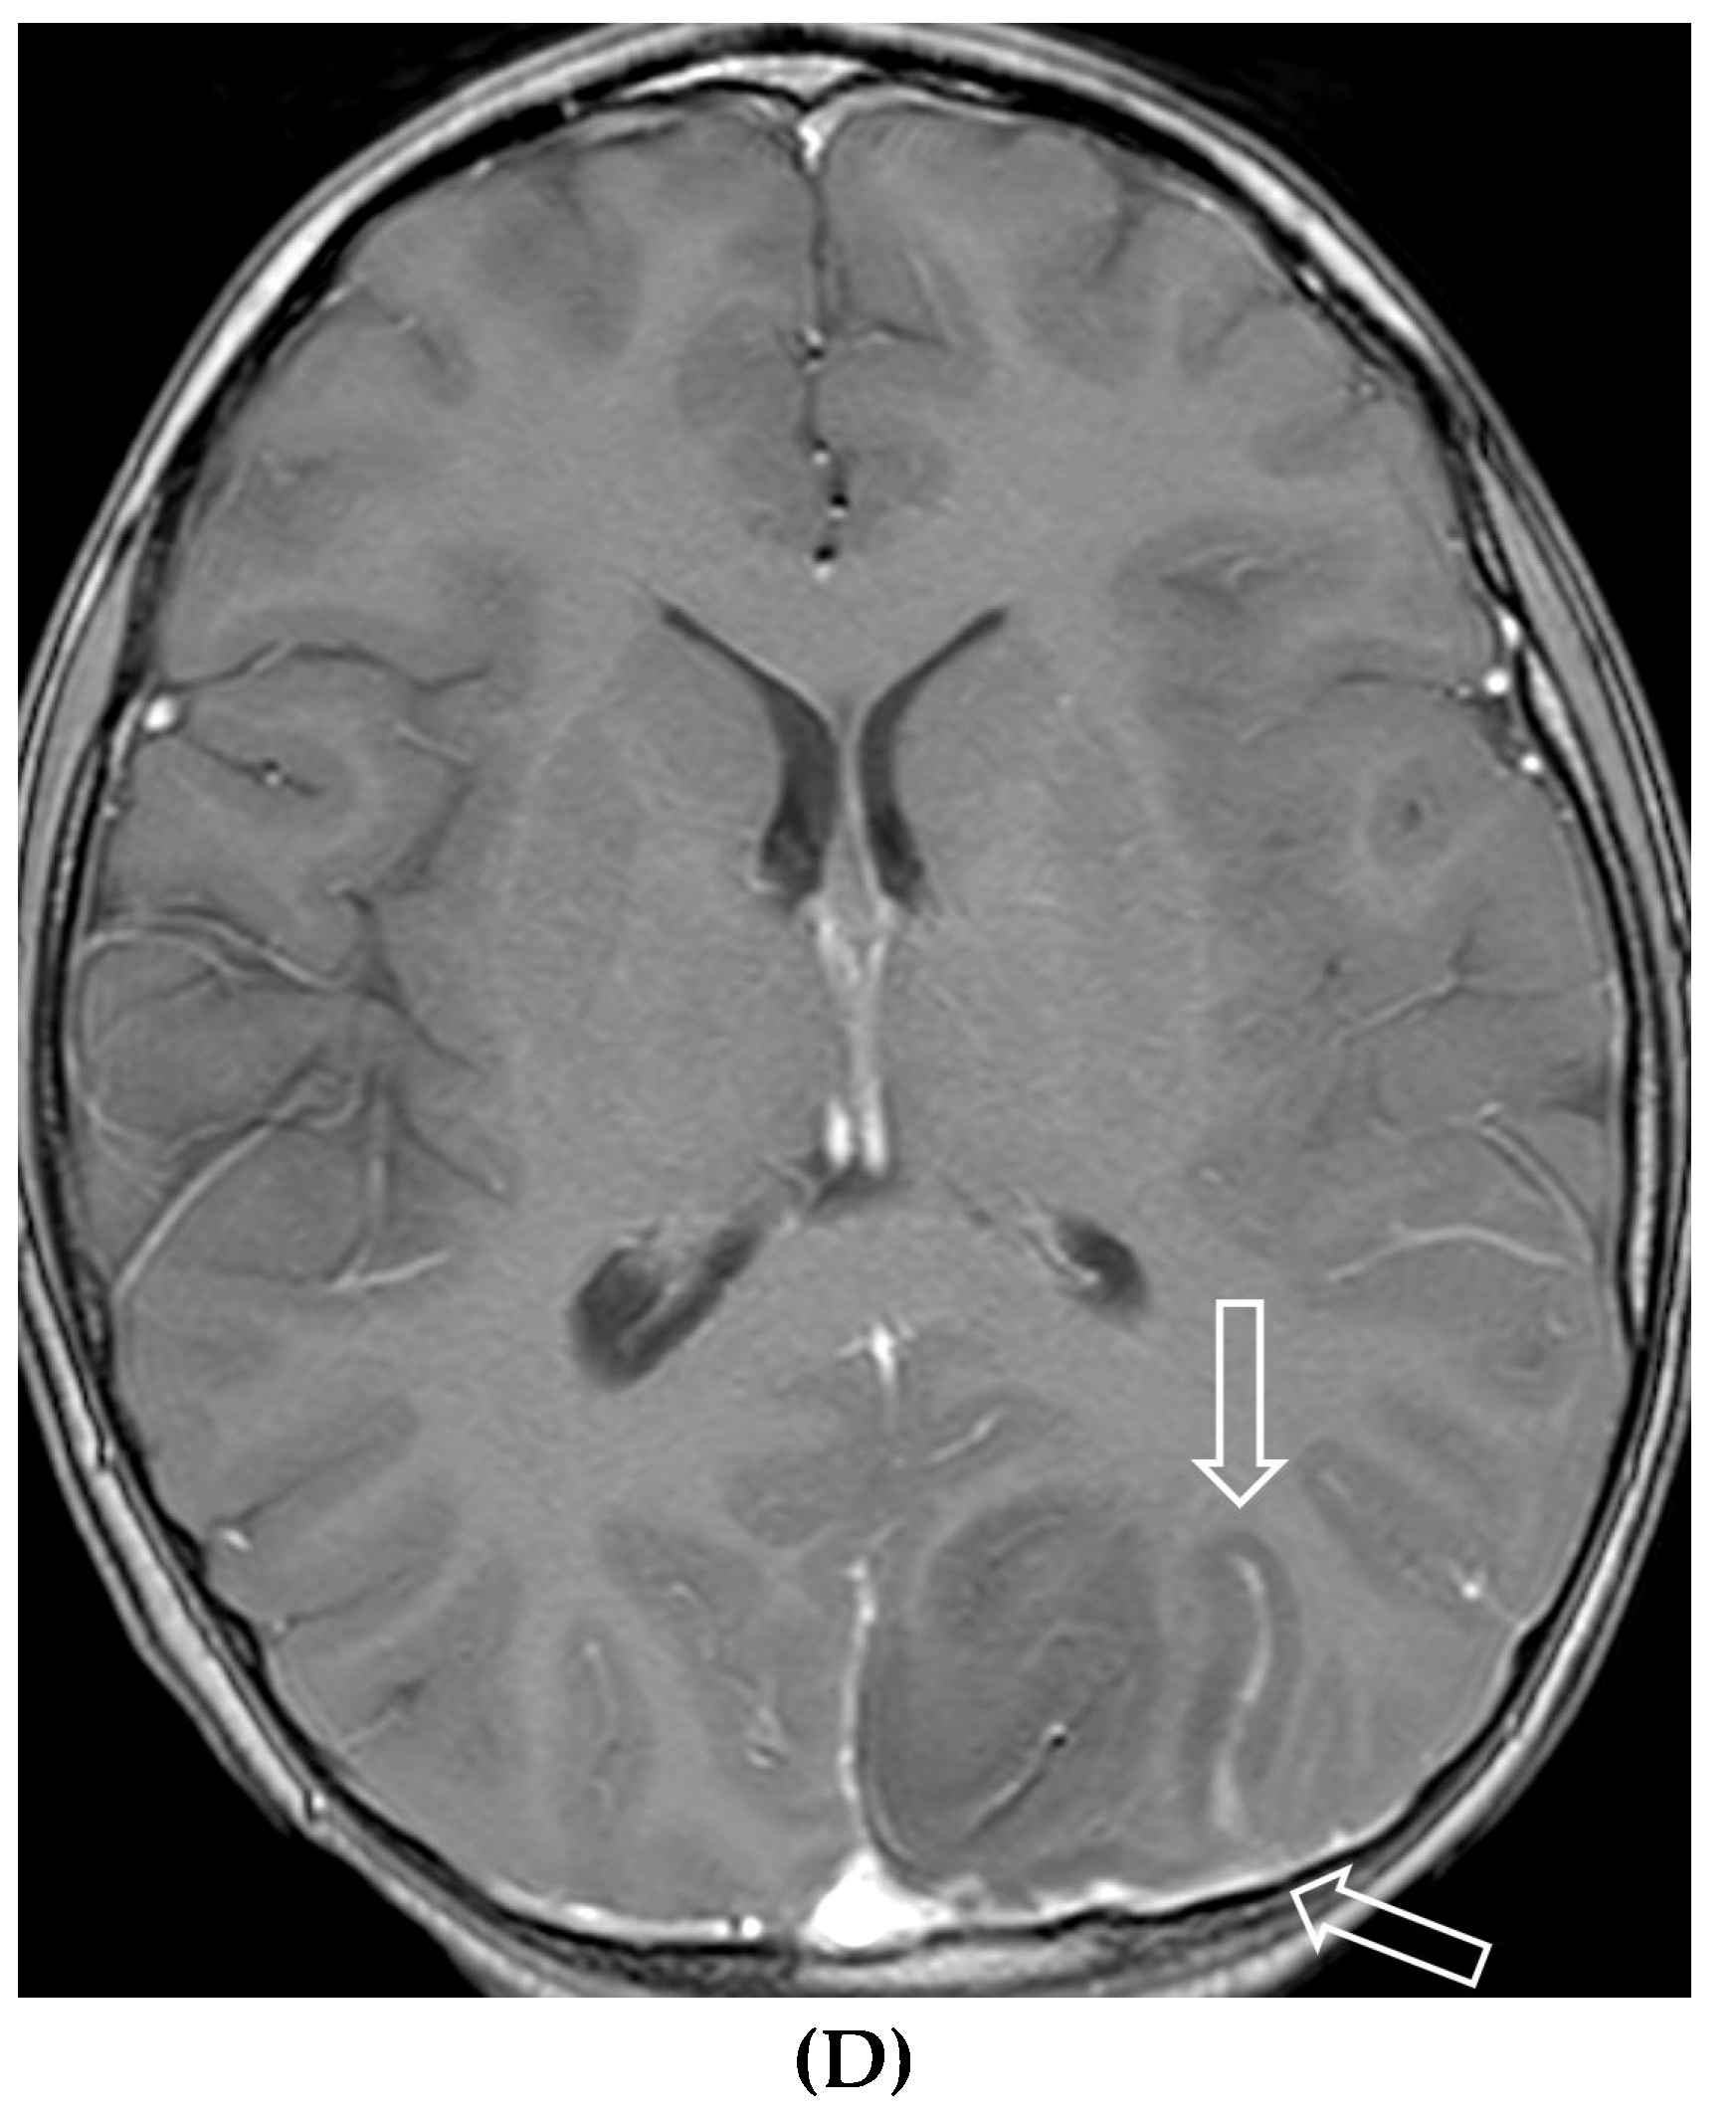

MOYA MOYA